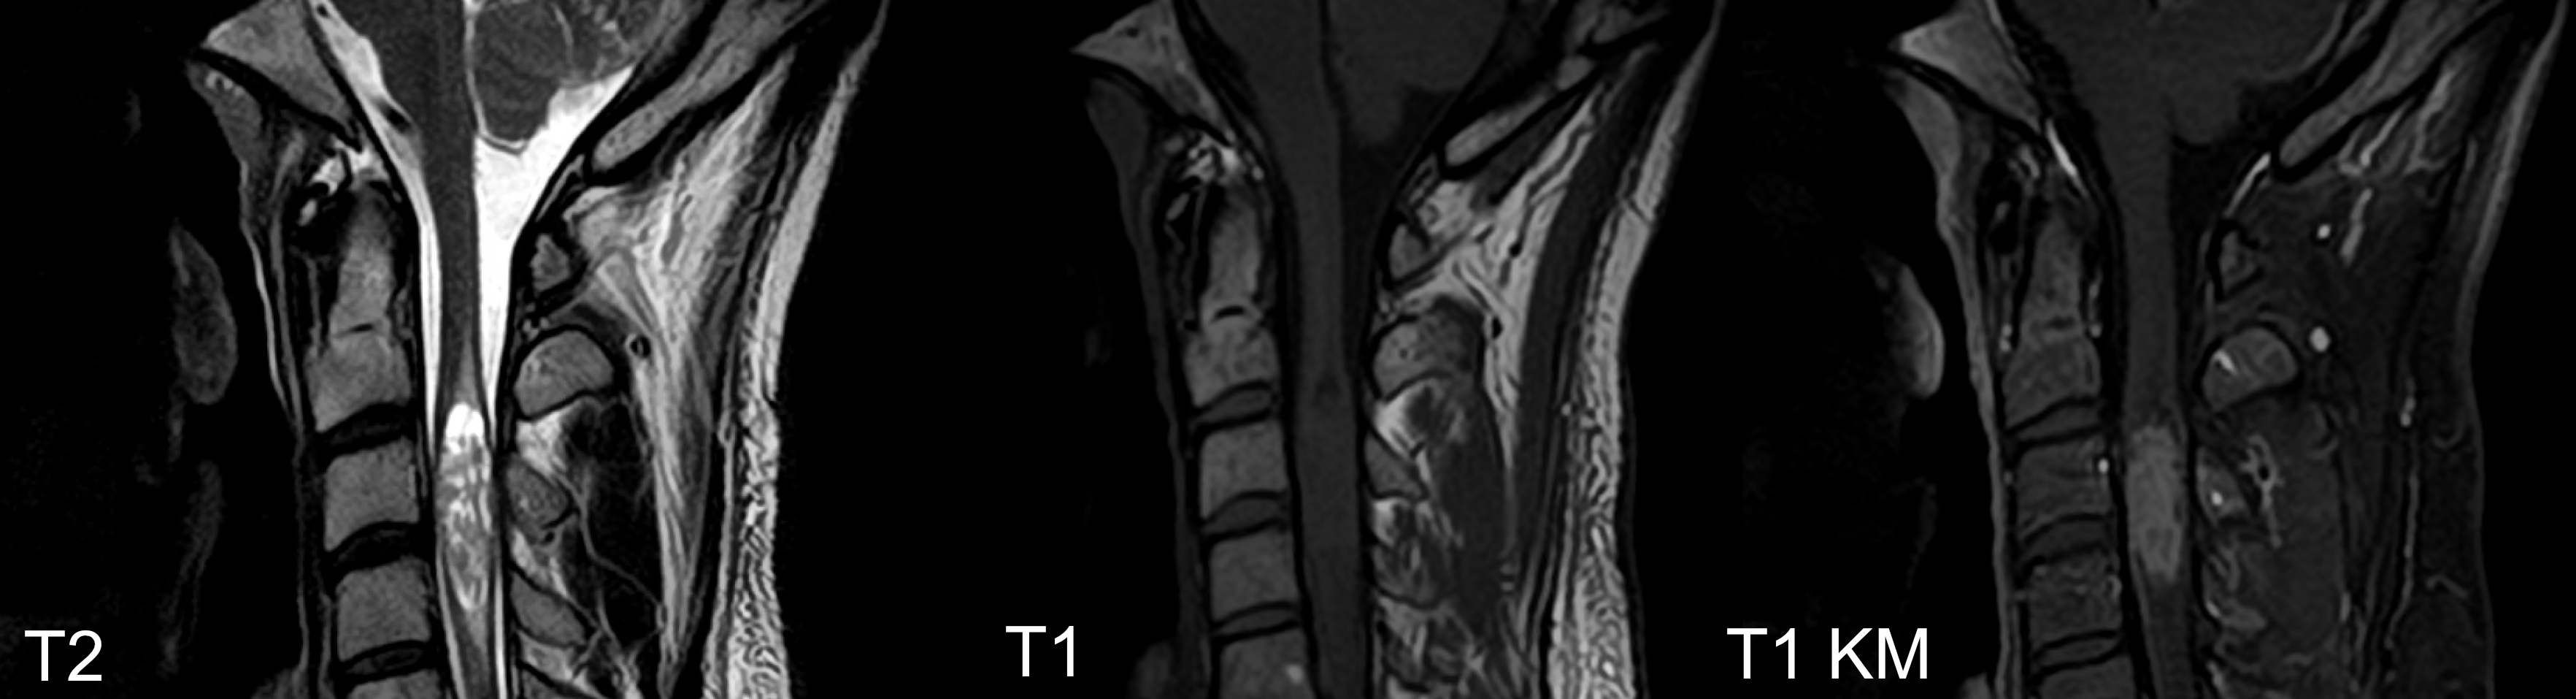

Bildgebend unterscheiden sich Ependymome von Medulloblastomen vor allem durch die häufige Kalzifikation, welche bei Medulloblastomen nur in weniger als 10 % der Fälle vorkommt[^2]. Ebenso zeigen sich Ependymome häufig inhomogen in der T1 Sequenz und die exophytische Komponente zeigen sich bei Ependymomen oft hyperintenser in der T2 Sequenz[^2]. Ependymome können in der MRT Bildgebung eine Diffusionsrestriktion aufweisen, was jedoch bei Ependymomen deutlich seltener als bei Medulloblastomen vorkommt[^4].

Ein mögliches, aber nicht sicheres, Unterscheidungsmerkmal zwischen spinalen Ependymomen und Astrozytomen ist das Vorhandensein einer Syringohydromyelie bei Ependymomen, welche bei Astrozytomen nur sehr selten vorkommt[^7].

Intramedulläre Ependymome

Ependymome können entlang des gesamten Rückenmarks auftreten und sind die häufigsten Gliom des kaudalen Rückenmarks, Conus und Filum. Es handelt sich um langsam wachsende Tumore.